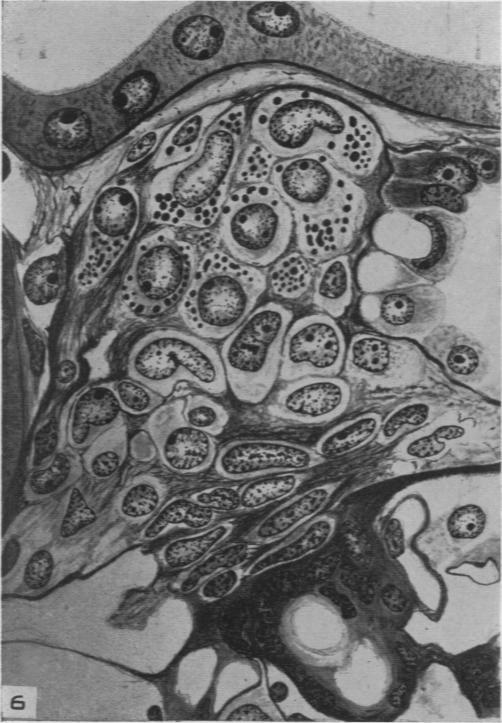

The Renal Arteriolar Changes in the Anuric Crush Syndrome.

Am J Pathol. 1947 Jul;23(4):513-29.